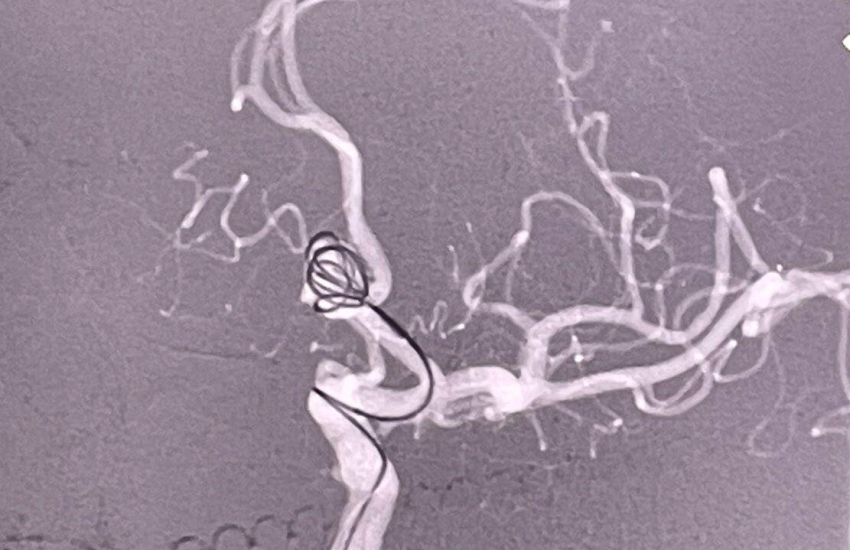

Цими днями наші лікарі відділення інтервенційної радіології разом з провідним фахівцем з ендоваскулярної нейрохірургії Чередниченко Юрієм Віталійовичем, к.мед.н., лікарем-нейрохірургом КП «Дніпропетровська обласна клінічна лікарня імені І.І. Мечникова» Дніпропетровської обласної ради» та за підтримки компаній Medtronic успішно виконали ендоваскулярне виключення мікроспіралями аневризми артерії головного мозку, попередивши інсульт у пацієнта.

За словами завідувача відділення інтервенційної радіології Черкаської обласної лікарні Паляничка Дмитра Андрійовича, операцію було виконано найбезпечнішим і сучасним способом, зробивши прокол артерії кисті пацієнта, через який хірурги потрапили до цільової судини в головному мозку та імплантували мікроспіралі, вилучивши аневризму з кровообігу та попередивши її розрив та інсульт. Хірург зауважив, що такі операції, на відміну від відкритих, з трепанацією черепу, в рази знижують ризик як самої операції, так і післяопераційних ускладнень. Вже через пару годин після операції пацієнт повернувся до звичайного життя та був виписаний на другу добу додому.